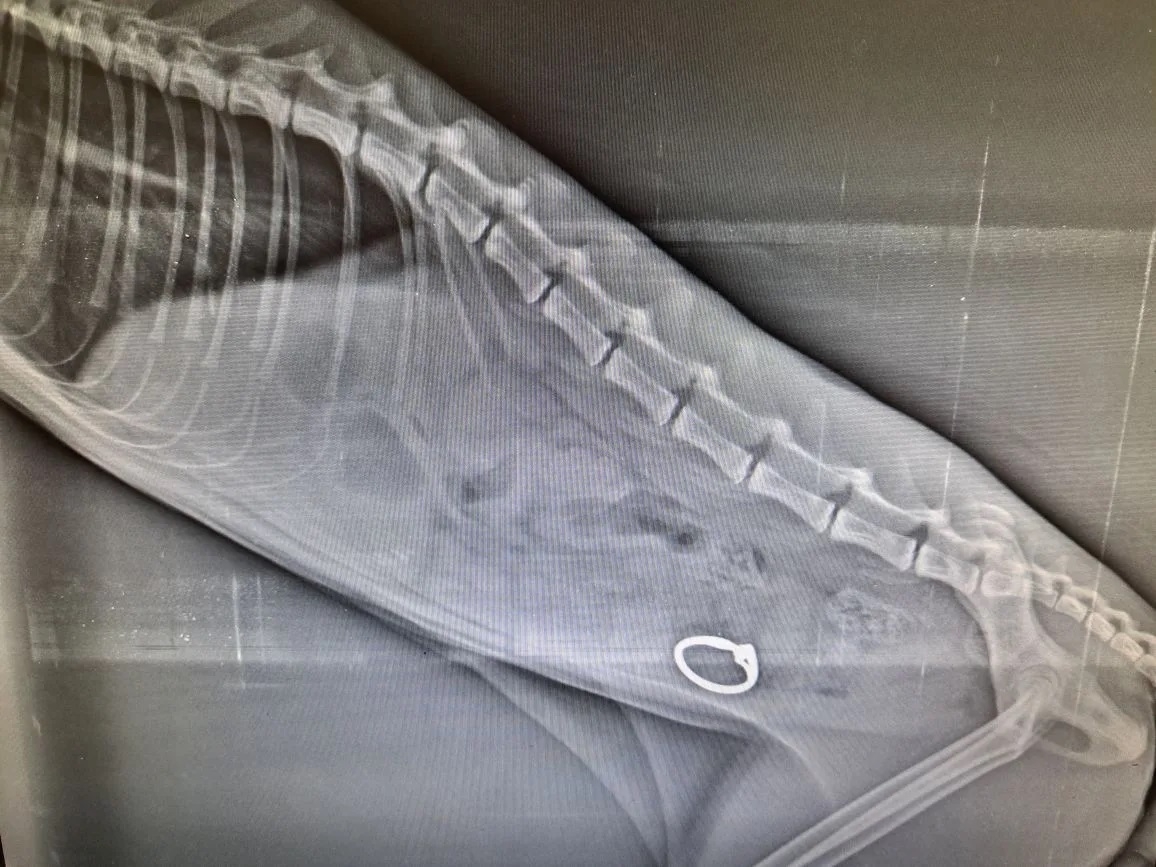

Рентген показал, что в толстом отделе кишечника у кота находится инородное дело. Ветеринары провели экстренную операцию. Из Масика достали кольцо с камнем. Металл частично окислился. У кота уже пошло осложнение из-за длительного пребывания в кишечнике украшения. Некротические ткани удалили, рассказали в ГБУ АО " Астраханская областная ветеринарная станция".